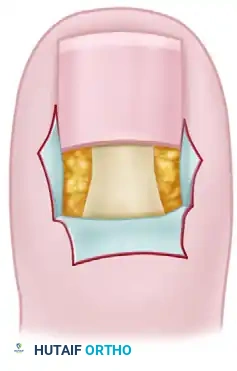

The cornerstone of successful perionychial surgery lies in a profound understanding of the nail unit's anatomy. The procedure typically involves a precise wedge resection of the nail plate, the underlying nail bed, and the hypertrophic nail fold. However, the most notorious and frequent complication of wedge resection is the postoperative recurrence of nail spicules.

Clinical Pearl: The crucial factor in preventing the formation of recurrent nail spicules is the absolute and complete removal of the germinal matrix at the lateral horns. Because the apex of the surgical wedge—and consequently the narrowest area of resection—is located at the most critical tissue requiring excision, meticulous surgical technique is paramount.

Pathophysiology of Recurrence

When performing a partial nail fold removal, the surgeon creates a wedge excision. The base of this wedge is distal, and the apex is proximal, extending deep beneath the eponychium. The anatomical lateral horns of the germinal matrix curve proximally and laterally, often extending further than visually apparent. If the apex of the surgical wedge fails to capture the entirety of this lateral horn, the retained germinal matrix cells will continue to produce keratinized tissue, resulting in a sharp, highly symptomatic nail spicule that pierces the healing paronychium.